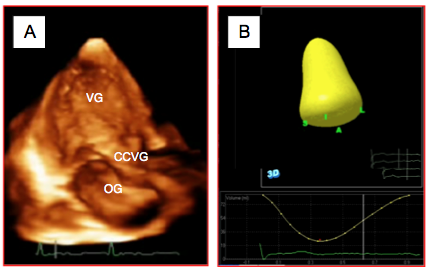

En imagerie bidimensionnelle, la détermination du volume du VG n'est possible que par le biais d'approximations géométriques qui introduisent une marge d'erreur considérable. Au contraire, l'imagerie tridimensionnelle donne directement accès au volume de la cavité ventriculaire. L'acquisition est faite en vue mi-œsophage 0-120° en englobant la totalité du VG et en faisant attention de ne pas amputer l'apex. La définition de l'endocarde est semi-automatique. Les muscles papillaires ne sont pas pris en compte, comme dans les mesures 2D [6]. Une fois opérée la définition de l'endocarde, le système réalise off-line un moule tridimensionnel de la cavité et peut suivre son évolution au cours du cycle cardiaque (Vidéo). Ce calcul a une bonne corrélation avec la mesure de l’IRM, bien qu'il tende encore à sous-estimer le volume réel du VG (Figure 27.4) [5,13].

Vidéo: reconstruction 3D d'un moulage endocavitaire dynamique du VG au cours d'un cycle cardiaque; la courbe jaune au bas de l'écran représente l'évolution temporelle du volume ventriculaire.

Figure 27.4 : Calcul du volume ventriculaire gauche en 3D. A: reconstruction du VG et de l'OG à partir d'une vue transthoracique apicale. B: la détection automatique des contours de l'endocarde réalise un moule de la cavité du VG et calcule son volume en continu au cours du cycle cardiaque; l'évolution du volume est illustrée par la courbe jaune au bas de l'écran.

La comparaison entre la mesure 2D (règle de Simpson) et la reconstruction 3D montre que l'examen ETO 2D sous-estime systématiquement le volume d'au moins 6-10%; toutefois, cette infirmité ne suffit pas à modifier la répartition des cas en trois catégories de dilatation ventriculaire (normal, modéré ou sévère), ce qui est suffisant en clinique [12].

En imagerie bidimensionnelle, la détermination du volume du VG n'est possible que par le biais d'approximations géométriques qui introduisent une marge d'erreur considérable. Au contraire, l'imagerie tridimensionnelle donne directement accès au volume de la cavité ventriculaire. L'acquisition est faite en vue mi-œsophage 0-120° en englobant la totalité du VG et en faisant attention de ne pas amputer l'apex. La définition de l'endocarde est semi-automatique. Les muscles papillaires ne sont pas pris en compte, comme dans les mesures 2D [6]. Une fois opérée la définition de l'endocarde, le système réalise off-line un moule tridimensionnel de la cavité et peut suivre son évolution au cours du cycle cardiaque (Vidéo). Ce calcul a une bonne corrélation avec la mesure de l’IRM, bien qu'il tende encore à sous-estimer le volume réel du VG (Figure 27.4) [5,13].

Vidéo: reconstruction 3D d'un moulage endocavitaire dynamique du VG au cours d'un cycle cardiaque; la courbe jaune au bas de l'écran représente l'évolution temporelle du volume ventriculaire.

Figure 27.4 : Calcul du volume ventriculaire gauche en 3D. A: reconstruction du VG et de l'OG à partir d'une vue transthoracique apicale. B: la détection automatique des contours de l'endocarde réalise un moule de la cavité du VG et calcule son volume en continu au cours du cycle cardiaque; l'évolution du volume est illustrée par la courbe jaune au bas de l'écran.

La comparaison entre la mesure 2D (règle de Simpson) et la reconstruction 3D montre que l'examen ETO 2D sous-estime systématiquement le volume d'au moins 6-10%; toutefois, cette infirmité ne suffit pas à modifier la répartition des cas en trois catégories de dilatation ventriculaire (normal, modéré ou sévère), ce qui est suffisant en clinique [12].